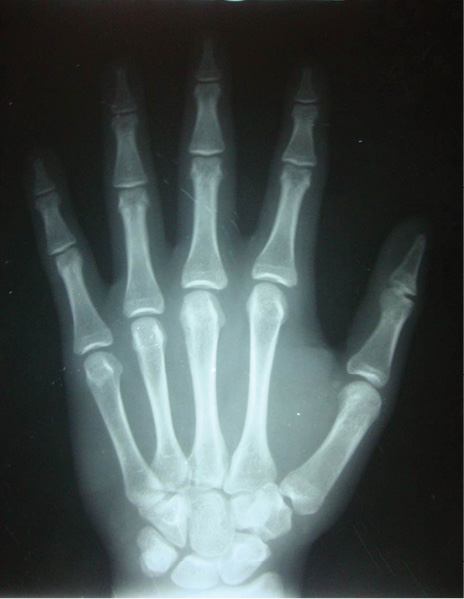

En el estudio imagenológico se observó en la radiografía de tórax, hipoplasia clavicular bilateral y tórax en forma de campana (Figura 2), en la radiografía panorámica se mostró la presencia de once dientes supernumerarios en el maxilar y nueve en la mandíbula (Figura 3), en la radiografía lateral cráneo se observó presencia de huesos wormianos landoideos (Figura 4); en la radiografía carpal se observó longitud simétrica de las falanges y sin alteraciones (Figura 5), de acuerdo con los hallazgos encontrados en el examen físico y la evaluación radiológica, se realizó la impresión diagnóstica de displasia cleidocraneal.